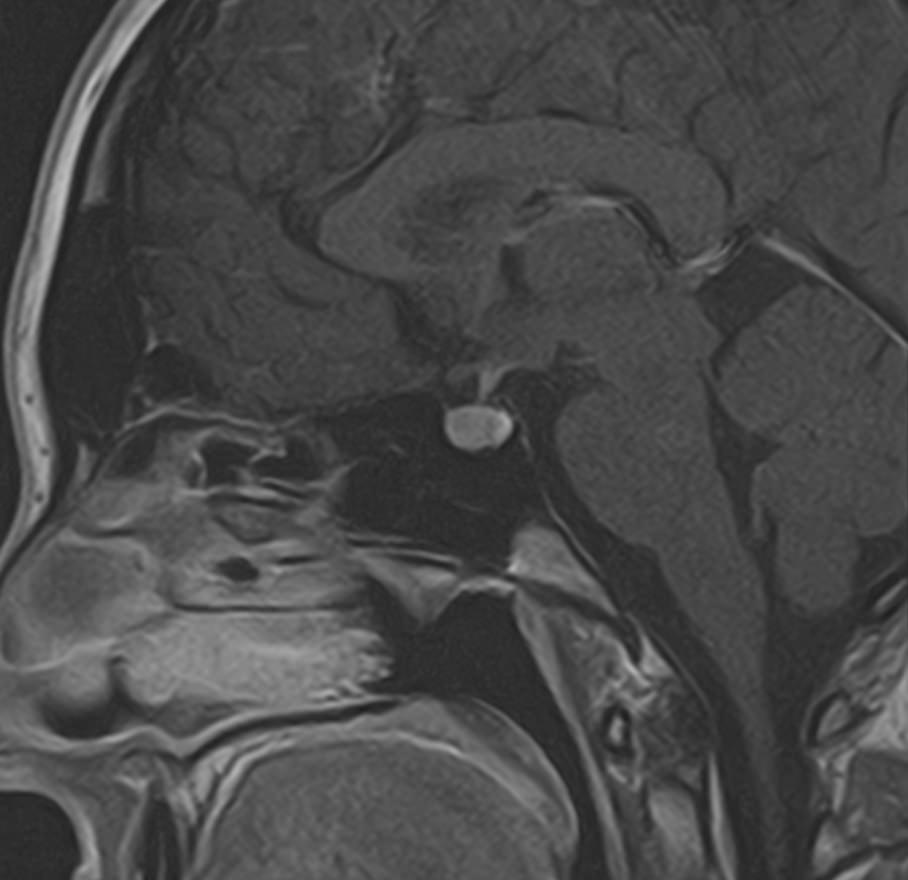

Поскольку гипофиз имеет очень маленькие размеры и расположен в глубине головы, досконально изучить его структуру можно только с помощью МРТ. Ни один другой из существующих методов визуализации не способен дать настолько четкие изображения и данные о состоянии гипофиза. Расшифровка результатов выполняется рентгенологом.

С помощью МРТ гипофиза можно создать его трехмерное изображение с высокой степенью детализации. Это позволяет обнаружить патологические изменения на самых ранних этапах, начиная от аномалий развития, сосудистых нарушений, воспалительных процессов и заканчивая опухолями разной природы.

МРТ гипофиза выполняется в нашей клинике выполняеется только с контрастным усилением, что повышает четкость получаемых изображений, а по особенностям распределения контрастного препарата в тканях можно с высокой точностью не только обнаружить доброкачественные и злокачественные опухоли, но и исследовать их локализацию, структуру, определить границы и заметить метастазы.

Чаще всего исследование проводится для диагностирования аденомы гипофиза и определения ее величины: микроаденомы (до 10 мм), макроаденомы (10—30 мм) и гигантской аденомы (более 30 мм). Также с его помощью обнаруживается неоднородностьструктуры, асимметрия границ, изменения положения воронки гипофиза и ее строения, а также деформации окружающих костных тканей.